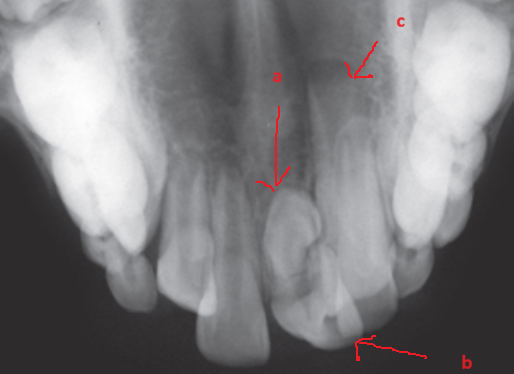

image 20231218155055 15 533x390 image 20231218155055 16 514x374 image 20231218155055 17 482x336

R21 chưa mọc, R11 đã mọc (a), Răng thừa (b), R22 (c) (b)Răng thừa thứ nhất, (a) răng thừa thứ 2, (c) R21 ngầm chưa mọc Phẫu thuật lật vạt:(a) răng thừa thứ 1, (b) R21 ngầm, (c) R22

image 20231218155055 19 502x340

Răng thừa thứ 1đã được nhổ Bộc lộ răng thừa thứ 2 Hình ảnh 2 răng thừa

Hình ảnh sau phẫu thuật 6 tháng, R21 đã mọc lên sau khi loại bỏ 2 răng thừa

Hình 4: Minh họa cho phẫu thuật lấy răng thừa đơn thuần ở một bé trai 9 tuổi